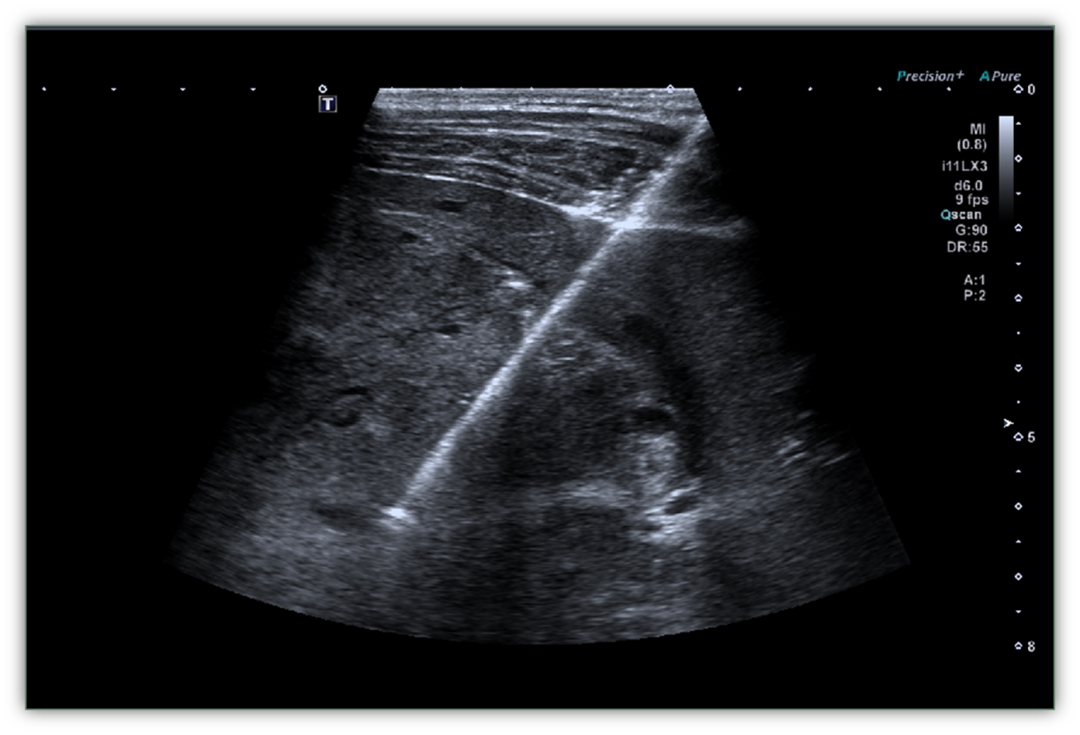

其实,想弄清肿块性质,未必需要承受手术创伤。超声引导下肿块穿刺活检,就是一种微创且精准的检查方式——通过取出少量组织进行病理分析,为诊断提供“金标准”,帮助医生和患者制定后续方案。

一、什么是超声引导下肿块穿刺活检?

这是一项“实时导航+微创取样”的精准检查技术,核心分三步:

1.动态定位(精准导航):医生通过超声实时观察肿块的位置、大小,与周围血管、脏器的关系,避开关键组织,确保安全。

2.微创取样(精准取材):在超声的实时引导下,将穿刺针准确插进肿块,取出少量组织样本。

3.病理诊断(明确性质):将样本送到病理科,通过显微镜观察细胞形态,判断肿块是良性、恶性,还是处于良恶之间的交界性病变。

只要超声能清晰显示肿块位置,并存在安全的穿刺路径,无论是甲状腺、乳腺等浅表部位,还是肝脏、肺部等深部器官,大多能通过这种方式明确诊断。